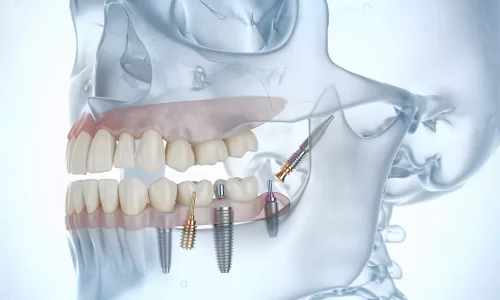

Pour de nombreux patients souffrant d'une perte osseuse sévère de la mâchoire supérieure, les implants dentaires traditionnels ne sont plus une option viable. Des années de perte de dents, des maladies parodontales ou des implants précédemment échoués peuvent résulter en une détérioration osseuse telle que les solutions conventionnelles ne fonctionnent tout simplement pas. C'est là que les implants zygomatiques interviennent — et chez Milim Dental, nous sommes spécialisés dans la délivrance de résultats réussis même pour les cas les plus défiants.

Découvrez comment les implants zygomatiques restaurent les dents en cas de perte osseuse importante de la mâchoire supérieure.